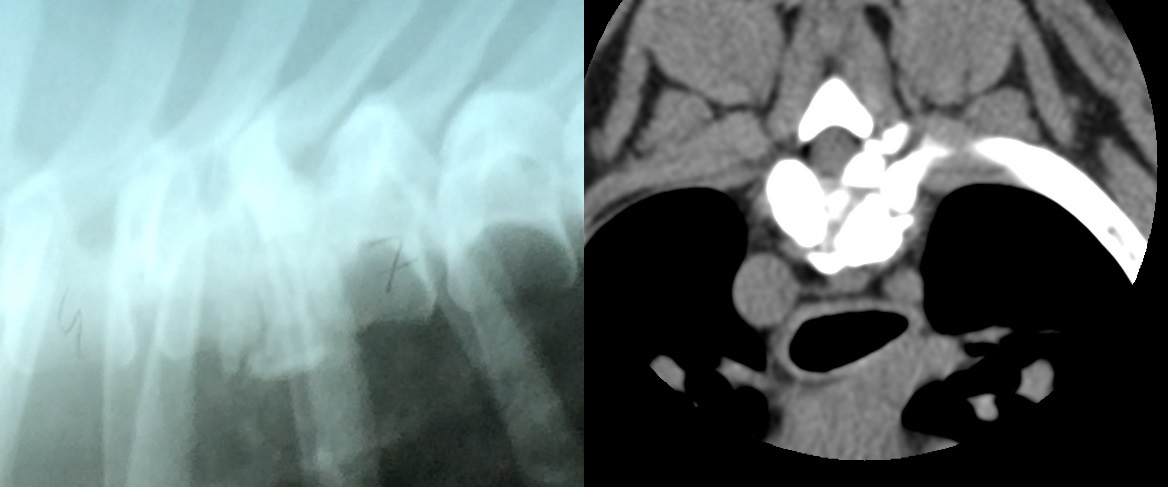

Fragmentwirbel im Röntgenbild und im CT

Ein diagnostizierter Keilwirbel ist keine sichere Aussage über die Gesundheit und Stabilität der Wirbelsäule. Eine

Beurteilung nutzt überhaupt nichts, wenn man nicht den gesamten Wirbel inkl. Durchfluss des Rückenmarks erkennen kann.

Begutachteter leichter Keilwirbel, der das Rückenmark schmerzhaft gequetscht hat

Zum Vergleich ein freier Wirbelkanal

Es sind in den letzten Jahren viele Bullys mit berühmten Pedigrees und unauffälligen Wirbelkörpern aufgrund von multiplen Bandscheibenvorfällen aufwändig saniert und in vielen Fällen tragischerweise euthanasiert worden. CT-Untersuchungen zeigen, dass sich Wirbel oftmals nicht ausbilden, es fehlt teilweise der gesamte Umschluss um den Wirbelkanal, es brechen Fragmente aus oder Teile des Wirbels sind erst gar nicht ausgebildet. Dies kann in seltenen Fällen sogar bei keilwirbelfrei begutachteten Wirbelkörpern aus seitlicher Aufnahme der Fall sein. Die Folgen für den Hund und vor allem für seinen möglichen Nachwuchs können verheerend sein.